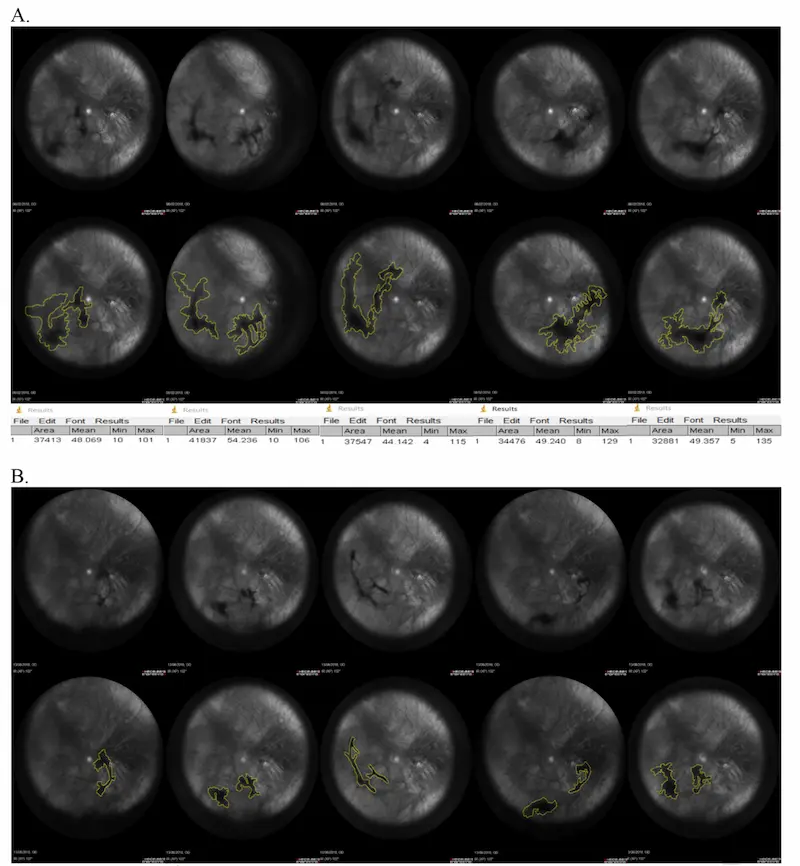

Here's a visual of what the fruit enzymes did in one patient.

Antioxidant Blend Reduces Floaters by 46.7%

Published in 2021 in Translational Vision Science & Technology, this study randomized people with floaters to either placebo or an active group.

Objective Measurements

People taking the antioxidant blend had huge improvements in visual discomfort.

After the 6 months, they rated their visual discomfort as improved by nearly 50%.

Here's a visualization of what the supplement did. On the top (A) is one individual before the study. The bottom (B) is them after 6 months of the supplement.

Results After Treatment

Improvement in Daily Life 46.7%

Persistent Discomfort Decrease 77.8%

Floater Area Decrease 17%